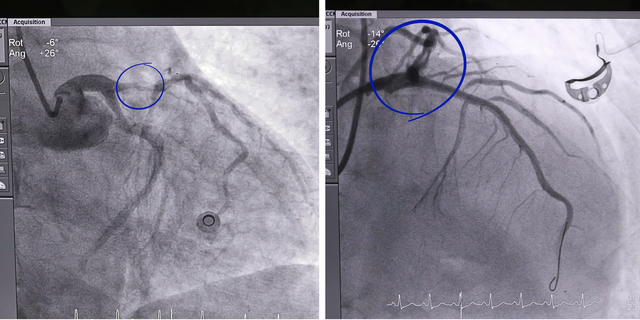

Bệnh nhân nhanh chóng được chuyển vào phòng can thiệp tim mạch, chẩn đoán nhồi máu cơ tim cấp ST chênh lên vùng trước rộng - một trong những thể bệnh tim mạch nặng nhất với tỉ lệ tử vong rất cao.

Ngay sau đó, các bác sĩ tiến hành chụp và xử lý tổn thương động mạch vành, đặt stent tái thông mạch máu nuôi. Đặc biệt, trong quá trình can thiệp, bệnh nhân vẫn tiếp tục có những thời điểm trở nặng, đòi hỏi ê-kíp vừa hồi sức vừa thực hiện kỹ thuật trong điều kiện hết sức căng thẳng.